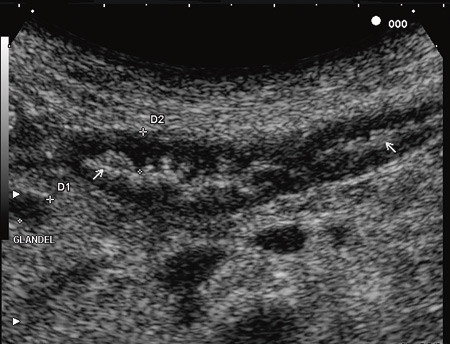

Kvinnen var på dette tidspunkt dehydrert og kakektisk, hun hadde gått ytterligere seks kilo ned i vekt og ble lagt inn i avdelingen for oppstart med antibiotika, ernæring og korreksjon av elektrolyttforstyrrelser. Hun følte seg konstant uvel i buken, hadde stadig diaré og en ekkel metallsmak i munnen. Ved innleggelsen viste blodprøvene CRP 79 mg/l, Hb 9,0 g/100 ml, K 2,9 mmol/l, Mg 0,49 mmol/l og albumin 23 g/l. Det ble ikke tatt spinalvæskeundersøkelse til analyse med polymerasekjedereaksjon. MR cerebrum var normal. CT abdomen viste uendrede funn. Ved hjelp av transabdominal ultrasonografi ble veggtykkelsen i tynntarmen målt til 4,7 mm, og det var økt ekkogenisitet i mucosa og submucosa, redusert tarmmotilitet, mural hyperemi samt multiple reaktive glandler i tarmkrøset (fig 3).

Ved transabdominal ultrasonografi av tynntarmen ses økt veggtykkelse (normal tarmvegg er 2 – 3 mm tykk) med hyperekkoisk mucosa og submucosa («hvit tarm»). I tillegg ses forstørrede mesenterielle lymfeknuter med økt ekkogenisitet. Man antar at lipidansamlingen sekundært til stase av lymfekarene kan forklare den økte ekkogenisiteten i tarmveggen og i lymfeknutene (11).